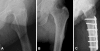

Case description: We report the cases of four women who sustained low-energy subtrochanteric or femoral shaft stress fractures while being on alendronate therapy for more than 5 years. All radiographs showed typical patterns consisting of a transverse fracture line with external cortical bone reaction and medial cortical spike. Alendronate discontinuation along with nonoperative treatment was sufficient for one patient, whereas surgical stabilization was required in three patients.